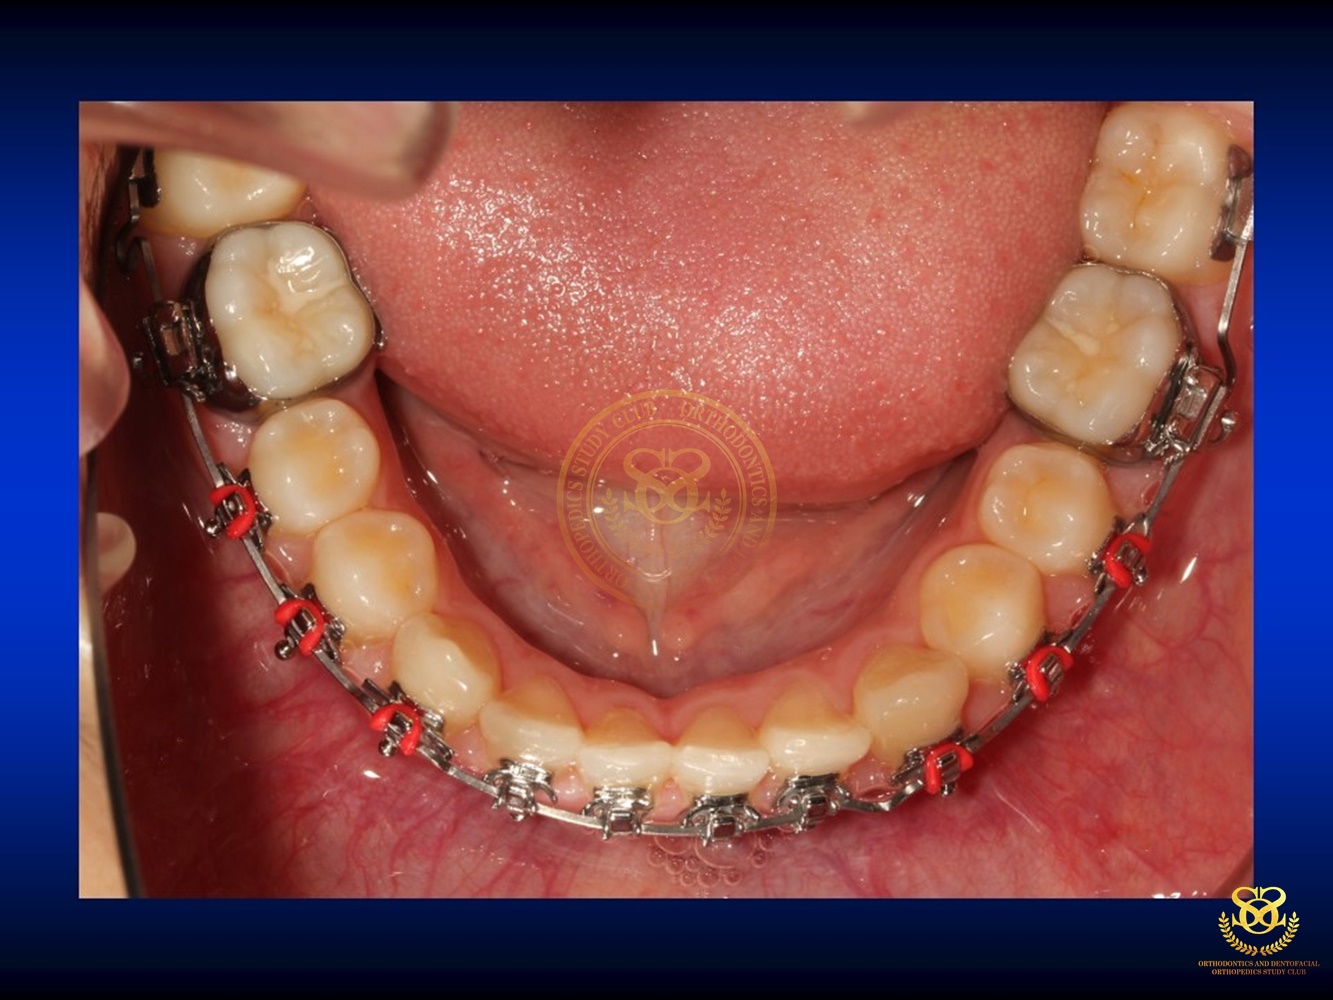

เคสตัวอย่าง Ben.Early Class III Tx.v.2018.CURRENT 2019-10-181168 views0 By Dr.Schwan Somsiri Share Share Share